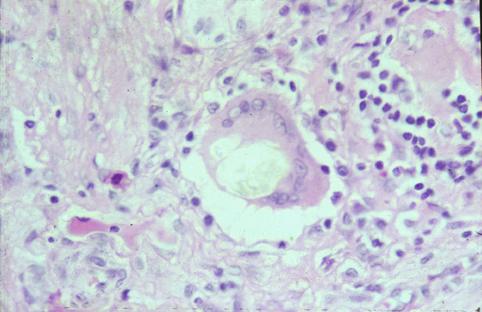

克罗恩(Crohn)病(肠)

伴有直肠瘘孔形成的小肠克罗恩病的切除病例

炎症性・溃疡性疾患/克罗恩病

小肠/空肠

病理切片(微观)